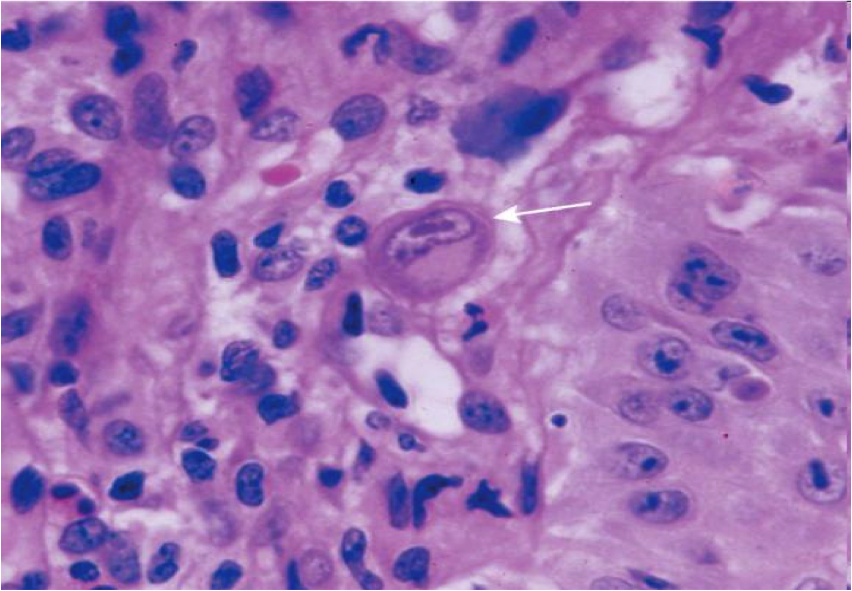

herpes esophagitis

lateral margin of ulcer

cowdry A intranuclear inclusions (Multinucleation, chromatin Margination, nuclear Molding)

CMV esophagitis

- Base of ulcer

- Lg intranuclear inclusion with granular cytoplasmic inclusions